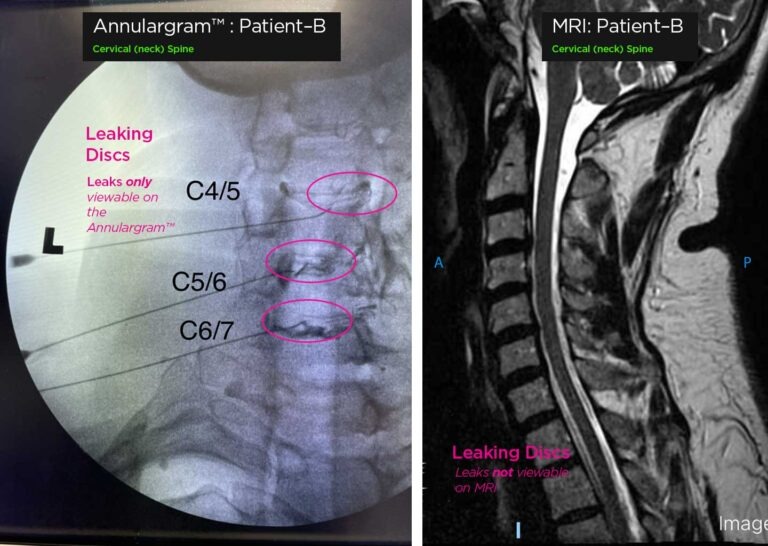

Because MRIs cannot reliably identify your pain source, we often rely on highly precise diagnostic injections. For your convenience, we’ll always work closely with your local Physician or find one close to you for your preliminary diagnostic workup.

If the diagnostic plan suggests your discs, we’ll review your MRI personally and use it to plan your Annulargram™ test. The Annulargram injects a trace amount of contrast into your disc’s outer annulus, allowing us to identify the minor leaks and tears missed by MRIs.

Neck (Cervical) Pain due to leaky discs can only be seen on an Annulargram™.

Comparison of cervical (neck) Spine with leaking discs on Annulargram vs MRI